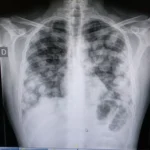

Desde el punto de vista radiológico, las alteraciones típicas incluyen un engrosamiento pleural nodular, irregular y unilateral, acompañado de diversos grados de derrame pleural también unilateral. La mayoría de los pacientes presentan afectación en el lado derecho, con aproximadamente un sesenta por ciento de los casos, mientras que la enfermedad bilateral es poco frecuente, observándose en solo un cinco por ciento. Las tomografías computarizadas son esenciales para evaluar la extensión de la enfermedad pleural y planificar el tratamiento. Además, la tomografía por emisión de positrones combinada con la tomografía computarizada (PET-CT) se utiliza para diferenciar con mayor precisión entre procesos benignos y malignos, mejorar la estadificación tumoral y seleccionar a los pacientes que podrían beneficiarse de intervenciones quirúrgicas más agresivas.